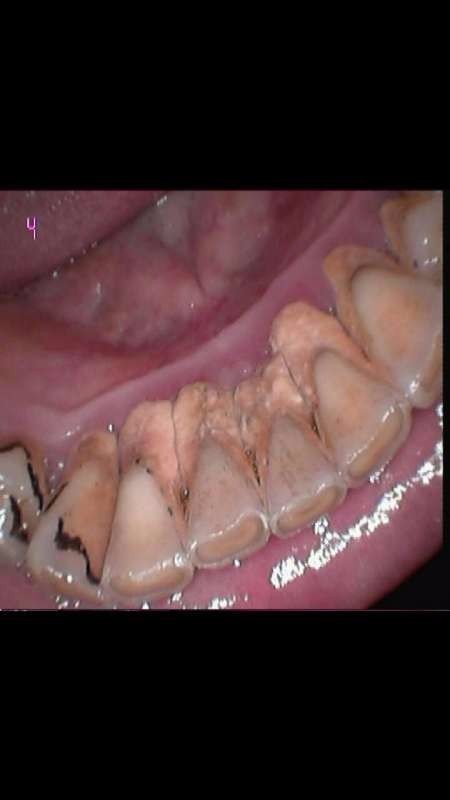

下前牙松动1度,要求洗牙后固定结扎

牙周夹板固定松动牙